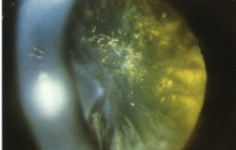

PSC

posterior subcapsular cataract

cataracts that have a significant effect on vision, especially with a small pupil

surgery may be necessary earlier on

no effect on RE

etiology: migration & thickening of lens epithelial cells in the posterior subcapsular space

trauma, chronic uveitis, chronic systemic steroid use